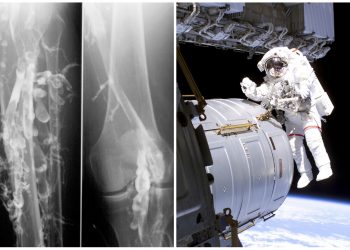

Leggi di piùPiede diabetico: cure tempestive

Per la prima volta, le Linee Guida Internazionali raccomandano una medicazione per il trattamento dei pazienti diabetici portatori di lesione...

Leggi di piùSindrome da classe economica e trombosi nello spazio

Prevenzione nello "Spazio" e nella vita di tutti i giorni Tutti noi, almeno una volta nella vita – soprattutto da...